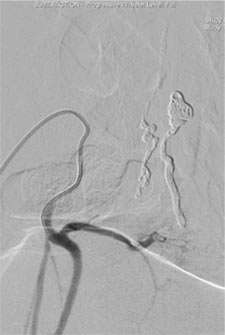

On the other hand, most dural or epidural AVFs are curable by surgery or catheter embolization. Our experience clearly shows “the sooner the treatment the better the outcome”. In our institution, minimally invasive catheter embolization was feasible in 75% of dural AVF cases. In the rest of 25% cases, surgical resection was performed. Both treatment methodologies result in a very high cure rate.

Figure 4: Catheter Embolization of a Spinal Dural AVF.

A microcatheter was navigated into a spinal dural AVF.

From the microcatheter, glue was injected into the AVF. After this, the lesion disappeared completely.